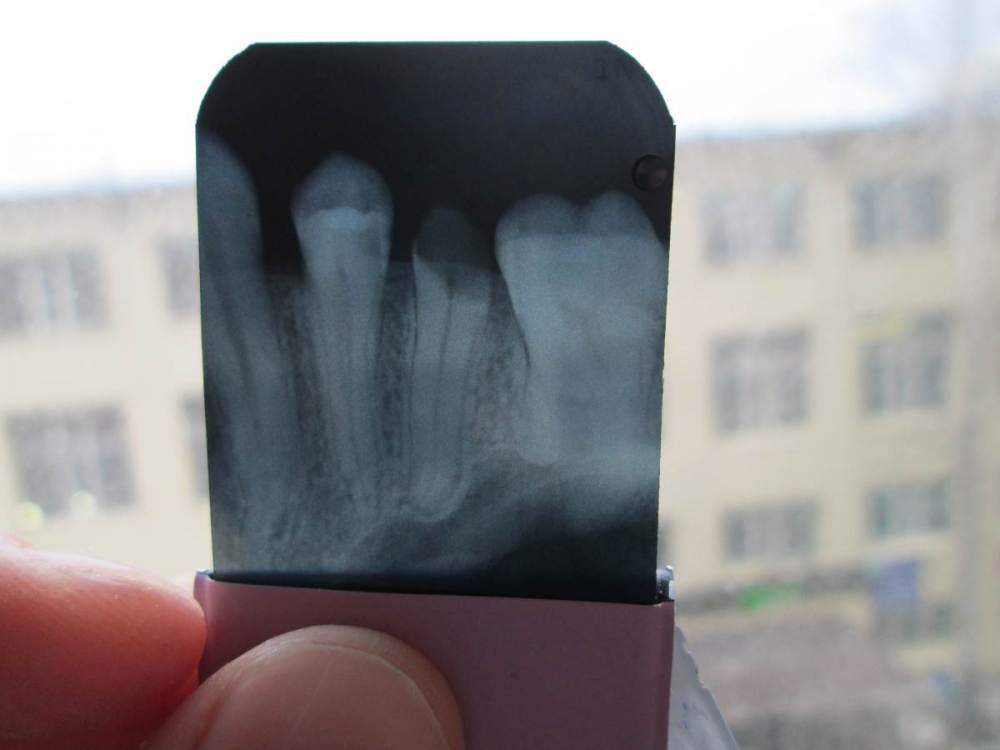

Nanny31 Опубликовано 29 апреля, 2021 Поделиться Опубликовано 29 апреля, 2021 Здравствуйте! Пару месяцев назад откололся премоляр (15-й), через месяц (работал) сходил в поликлинику. Сделали снимок, постучали, пожужжали, сказали удалять. Плюс насчитали 14 зубов к лечению. ОК. Один доктор хорошо, а два лучше. Пару дней назад, сходил в другую поликлинику, так же снимок (тот что меньше), итог - корень можно сохранить, метал. штифт + коронка. Плюс 8 зубов (на 6 меньше, предыдущего). Спросил про реставрацию, ничего не ответили, так же спросил про CEREC, тишина. Про реставрацию спросил не просто так. Уже был случай с моляром, было печальнее, но один врач сделал реставрацию, хотя другие так же говорили, что нужна коронка, штифт и т.д. Главное чтобы руки были прямые. Вопросы: 1. Что в данном случае будет оптимальным (коронка, реставрация, вкладка CEREC, что-нибудь иное)? 2. Перед анастезией дают ли направление на аллергопробу? Перед восстановлением моляра, была такая практика, частная клиника, но давали направление. Сейчас их уже нет. Ссылка на комментарий

red_butler Опубликовано 1 мая, 2021 Поделиться Опубликовано 1 мая, 2021 без очного осмотра ответить не получиться, возможно восстановление зуба потребует терапевтическую, ортодонтическую и/или хирургическую подготовку. Нсли судить только по рентгену, то удалять Ссылка на комментарий